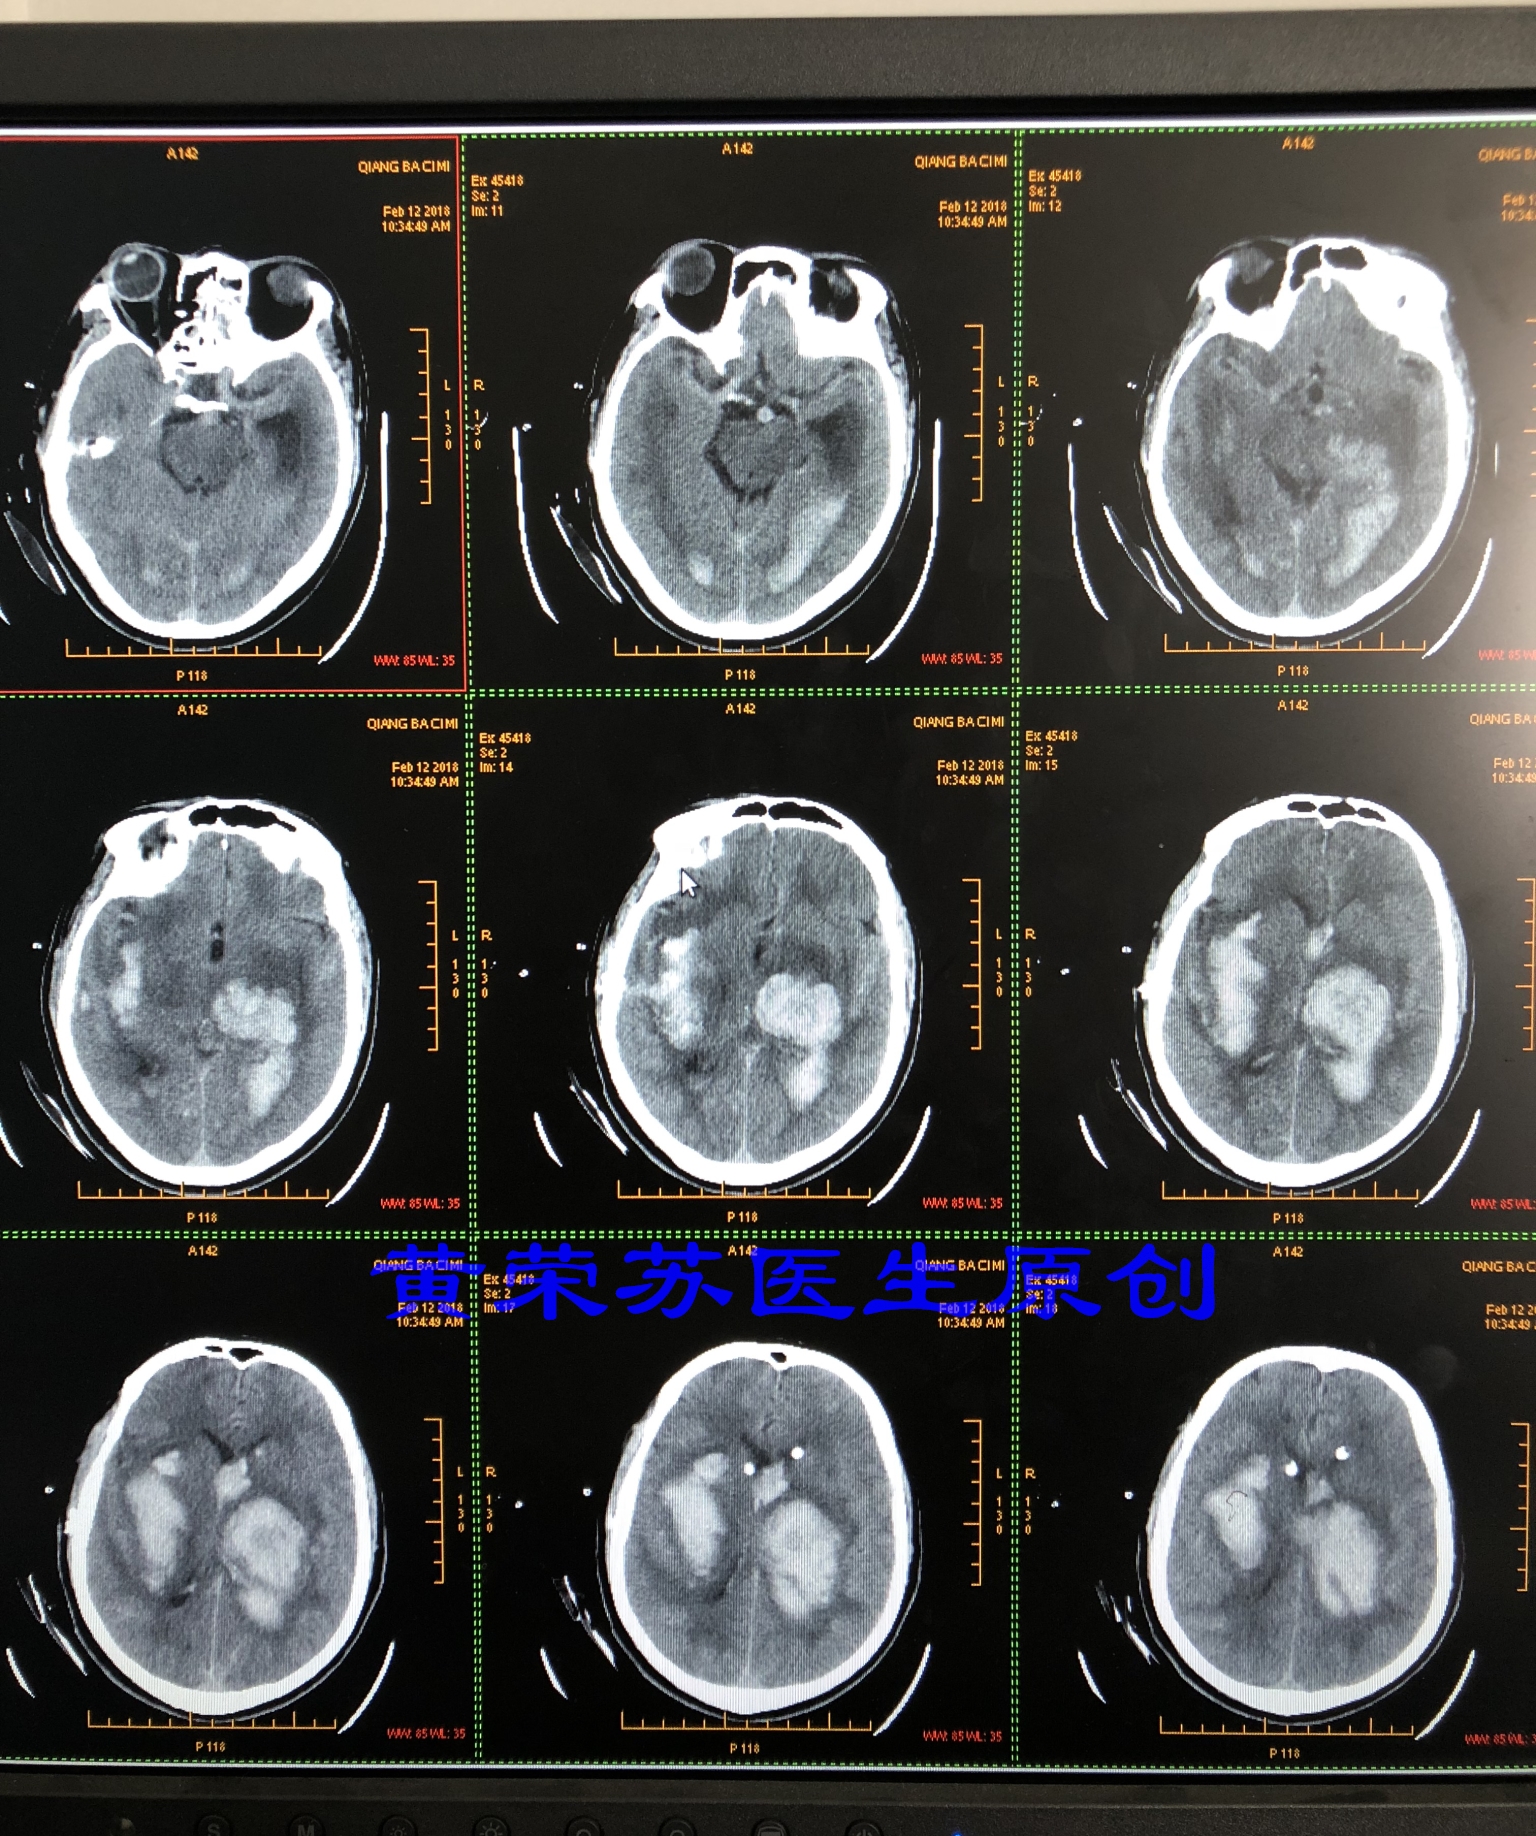

1、最常见的部位:基底节区脑出血,占60%~70%,该部位出血常出现三偏征(病灶对侧偏瘫、偏身感觉障碍、偏盲)。壳核和丘脑是高血压脑出血最常见的部位。

图一、典型的基底节区脑出血,破入脑室,形成脑室系统铸型